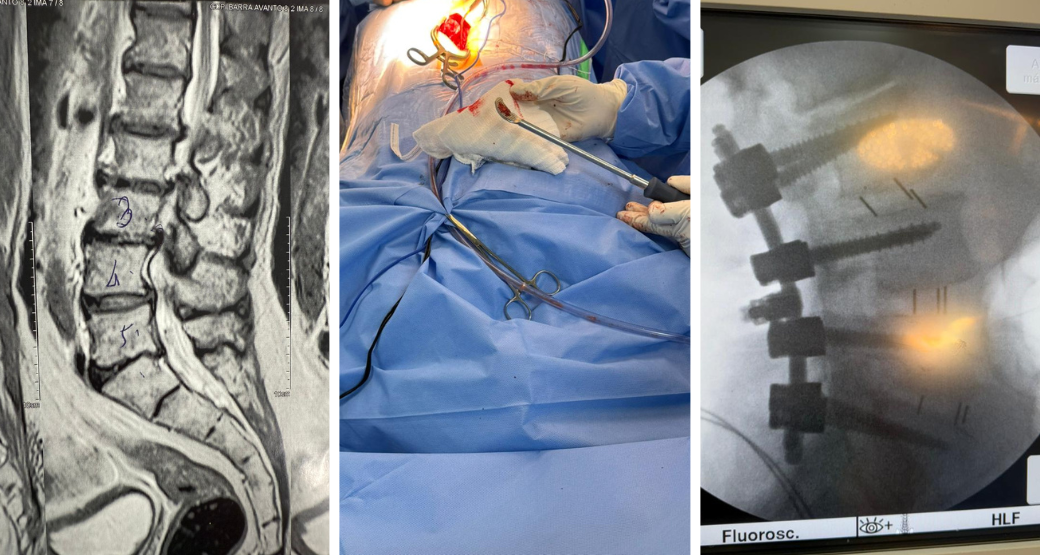

Descompressão endoscópica: Alívio para compressão radicular nas raízes L4 e L5?

“Sem dúvida... Realizamos com sucesso o procedimento em nosso paciente que sofria de dor lombar irradiada para membros inferiores e fraqueza muscular”, comemoram Edward Robert e Renato Bastos, cirurgiões ortopédicos.